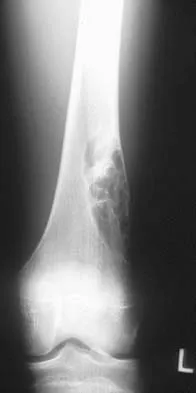

Figures 32a and 32b show the radiographs of an active 13-year-old boy who has persistent left thigh pain and a limp despite a trial of protected weight bearing. Management should consist of

Explanation

The plain radiographs show an eccentric metaphyseal lesion involving a long bone in a skeletally immature patient. The lesion is longer than it is wide, with distinctly lobular outer edges that are sclerotic. These findings are characteristic of a nonossifying fibroma. Small asymptomatic lesions may be followed clinically. Larger lesions that occupy greater than two thirds of the width of the shaft and are located in areas of high mechanical stress such as the femur are more prone to fracture than smaller lesions. Pain is often a sign of impending fracture or the presence of a small fracture that may not be apparent on radiographs. The natural history of the lesion is to resolve over a period of years. The procedure that would allow the patient to return to contact sports is curettage and bone grafting. Intralesional steroid injection has been advocated in the treatment of unicameral bone cysts and eosinophilic granuloma but not nonossifying fibromas. En block resection is not indicated for a benign lesion. Low-dose radiation therapy has been used for eosinophilic granuloma but not for nonossifying fibromas. Walker RN, Green NE, Spindler KP: Stress fractures in skeletally immature patients. J Pediatr Orthop 1996;16:578-584.